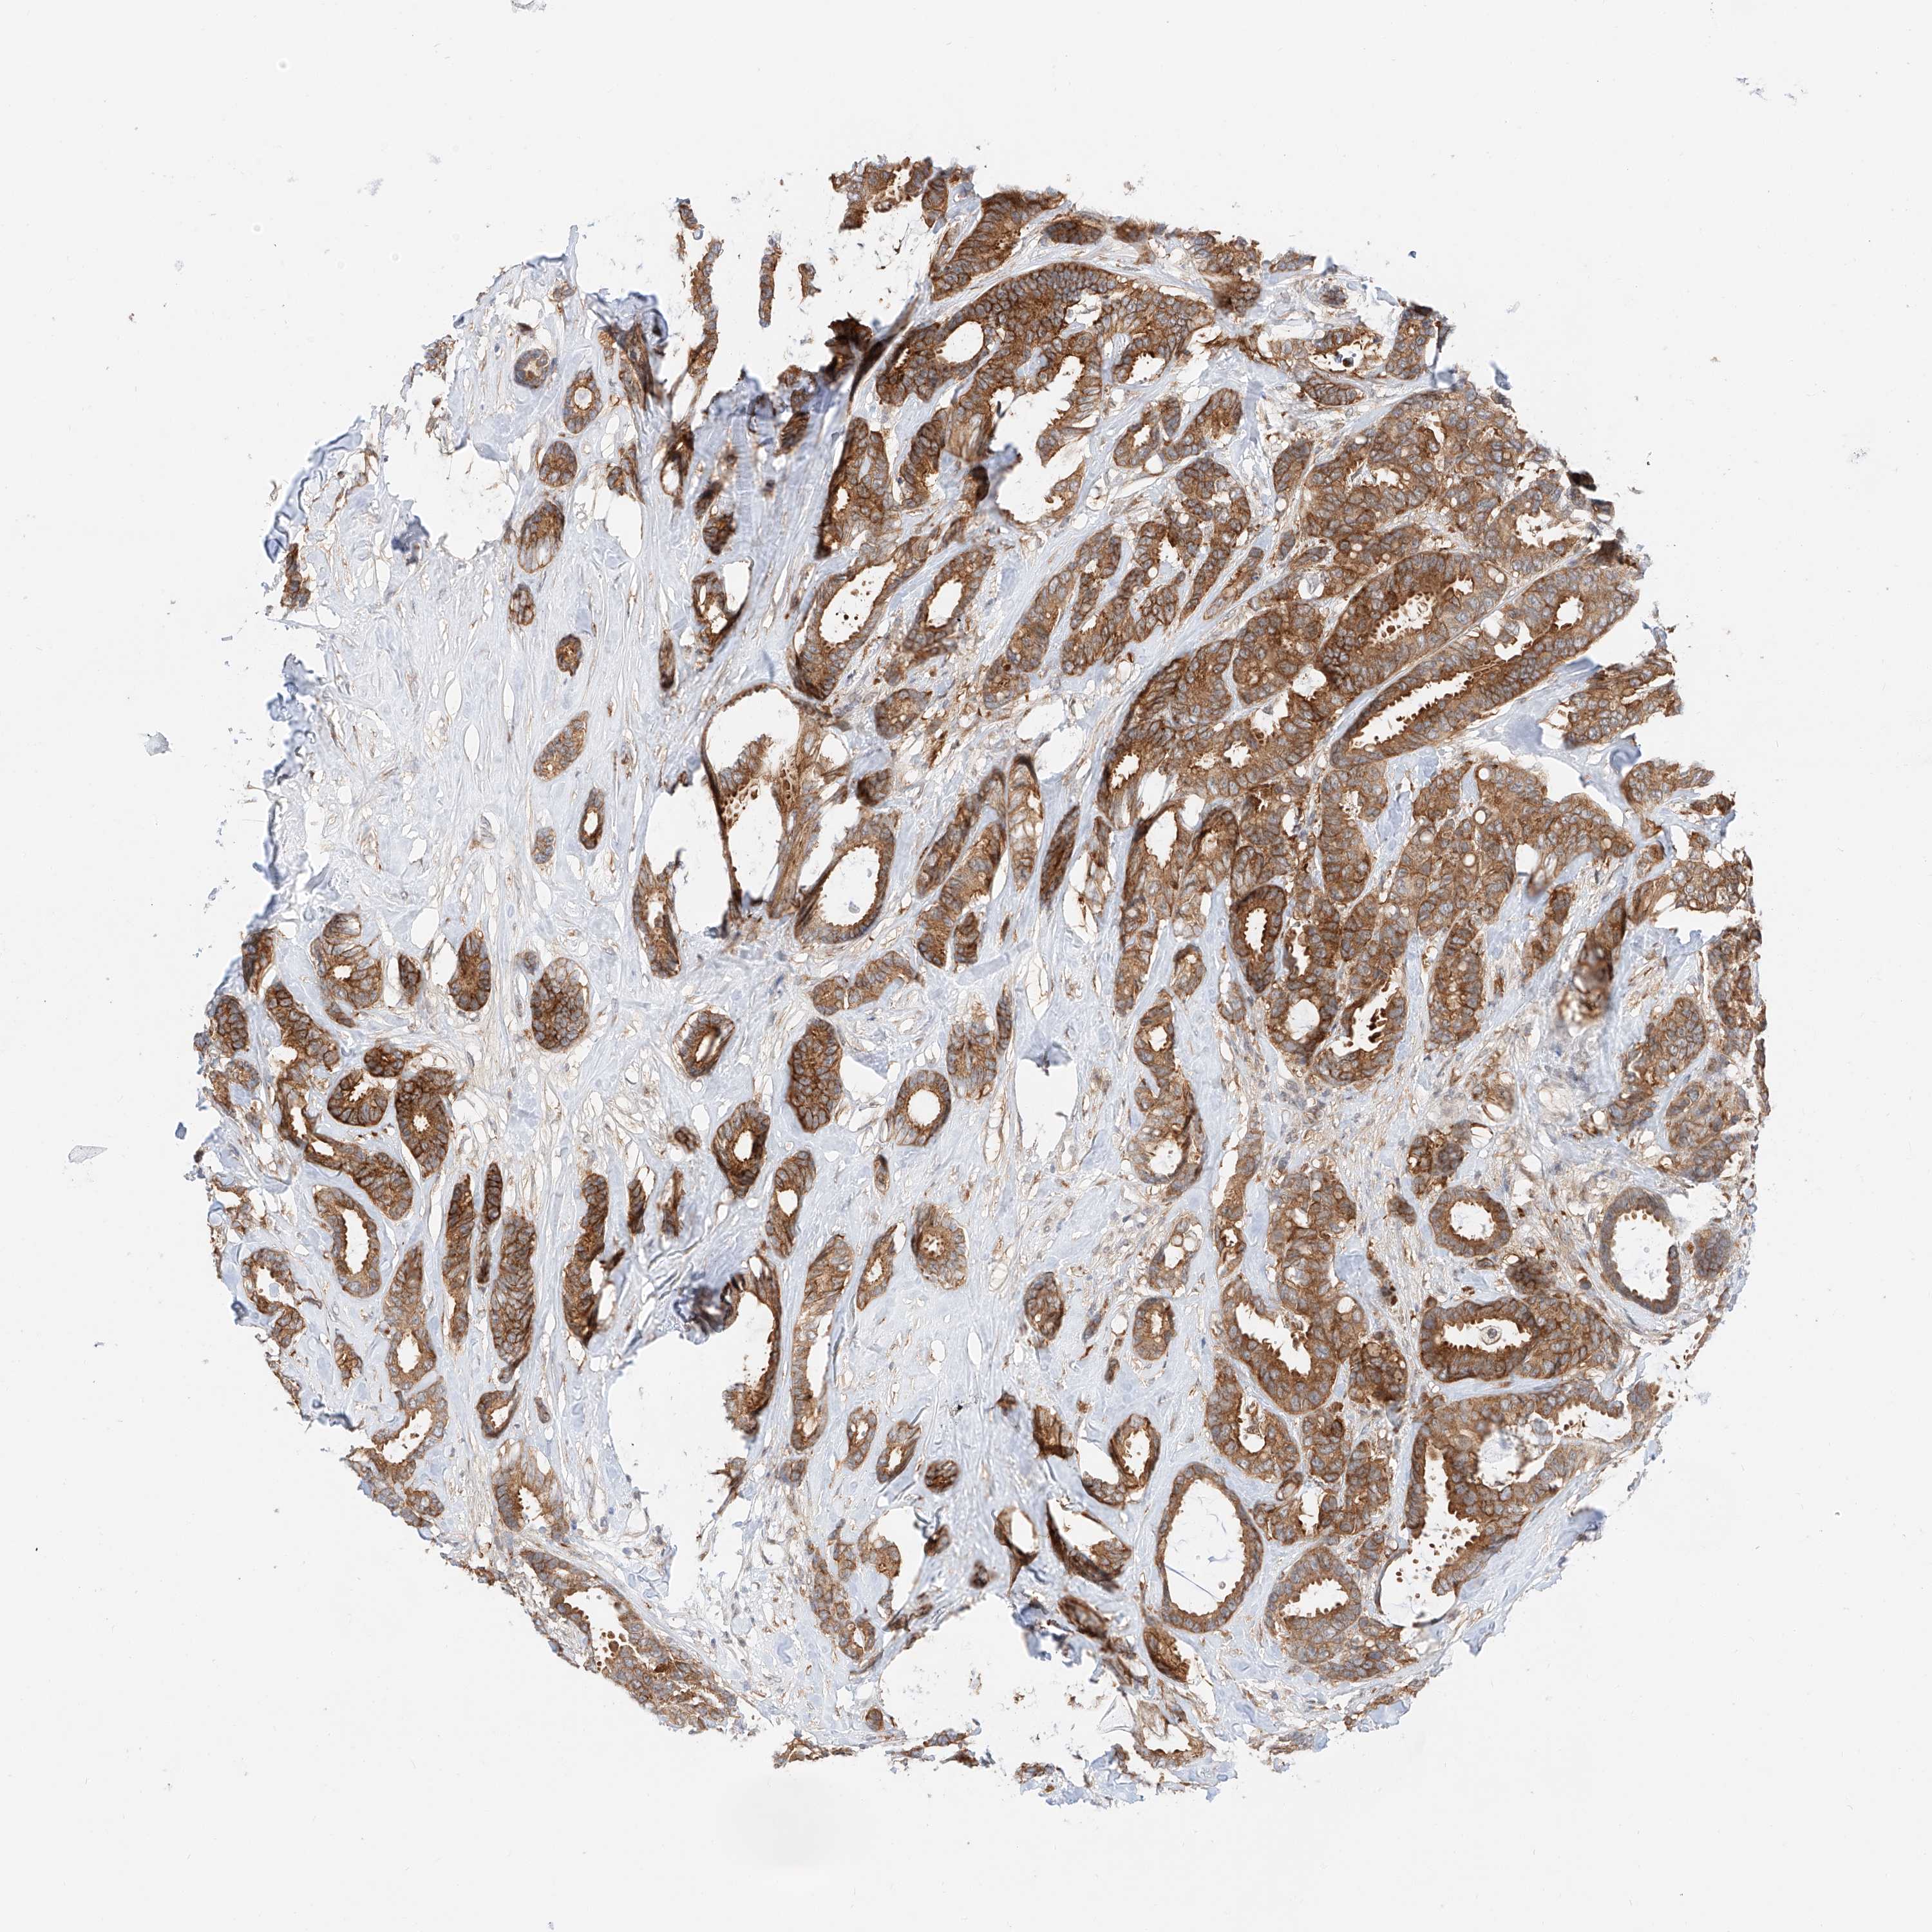

CANCER BREAST CANCER Show tissue menu

BRCA TCGA BRCA VALIDATION PROTEIN EXPRESSION